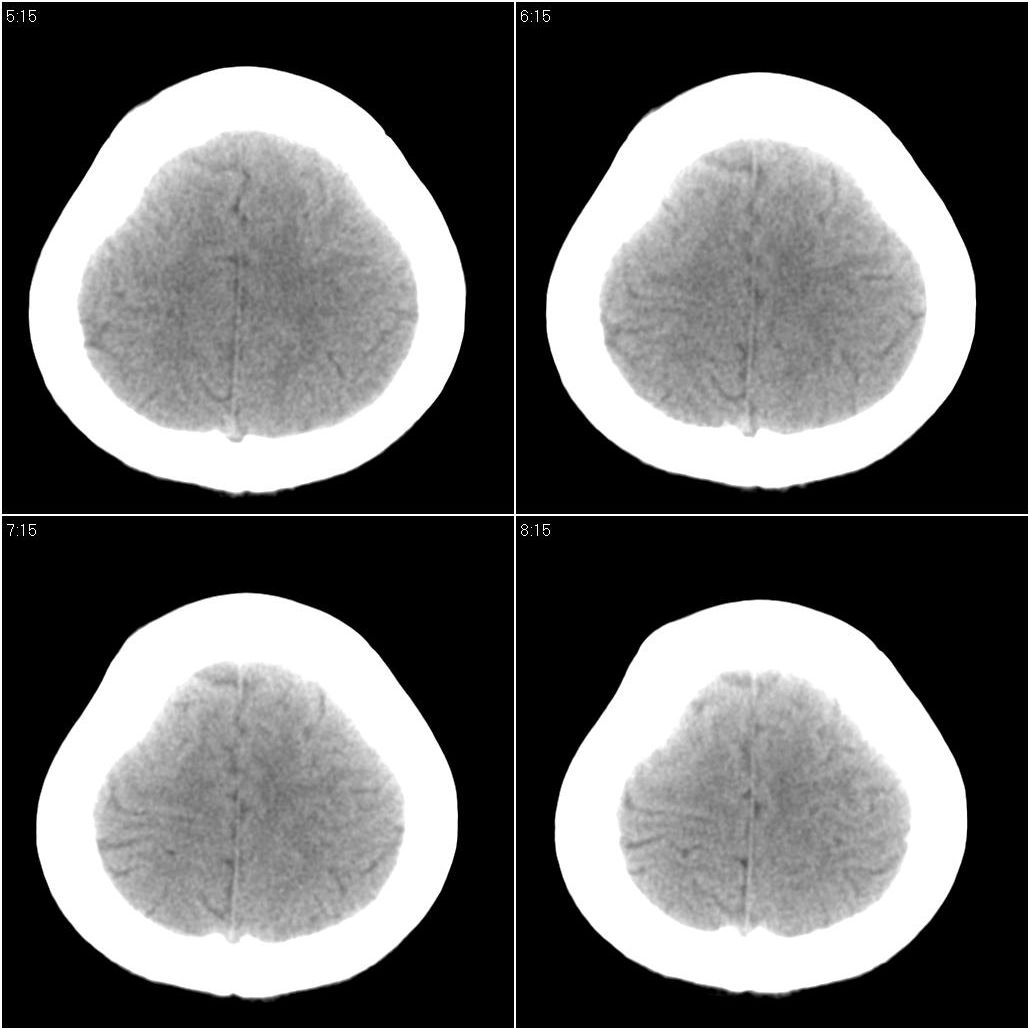

标题: CT16658:女性,49岁。发现右侧额部包块10余年。 [打印本页]

标题: CT16658:女性,49岁。发现右侧额部包块10余年。

支持骨瘤。病史长,病灶与颅骨密度一致,周围软组织没有异常改变。

右额部颅骨外板为主向外突出局限致密骨影,密度均匀,考虑额骨致密骨瘤

右侧额骨致密骨瘤。

考虑右侧额骨致密骨瘤。